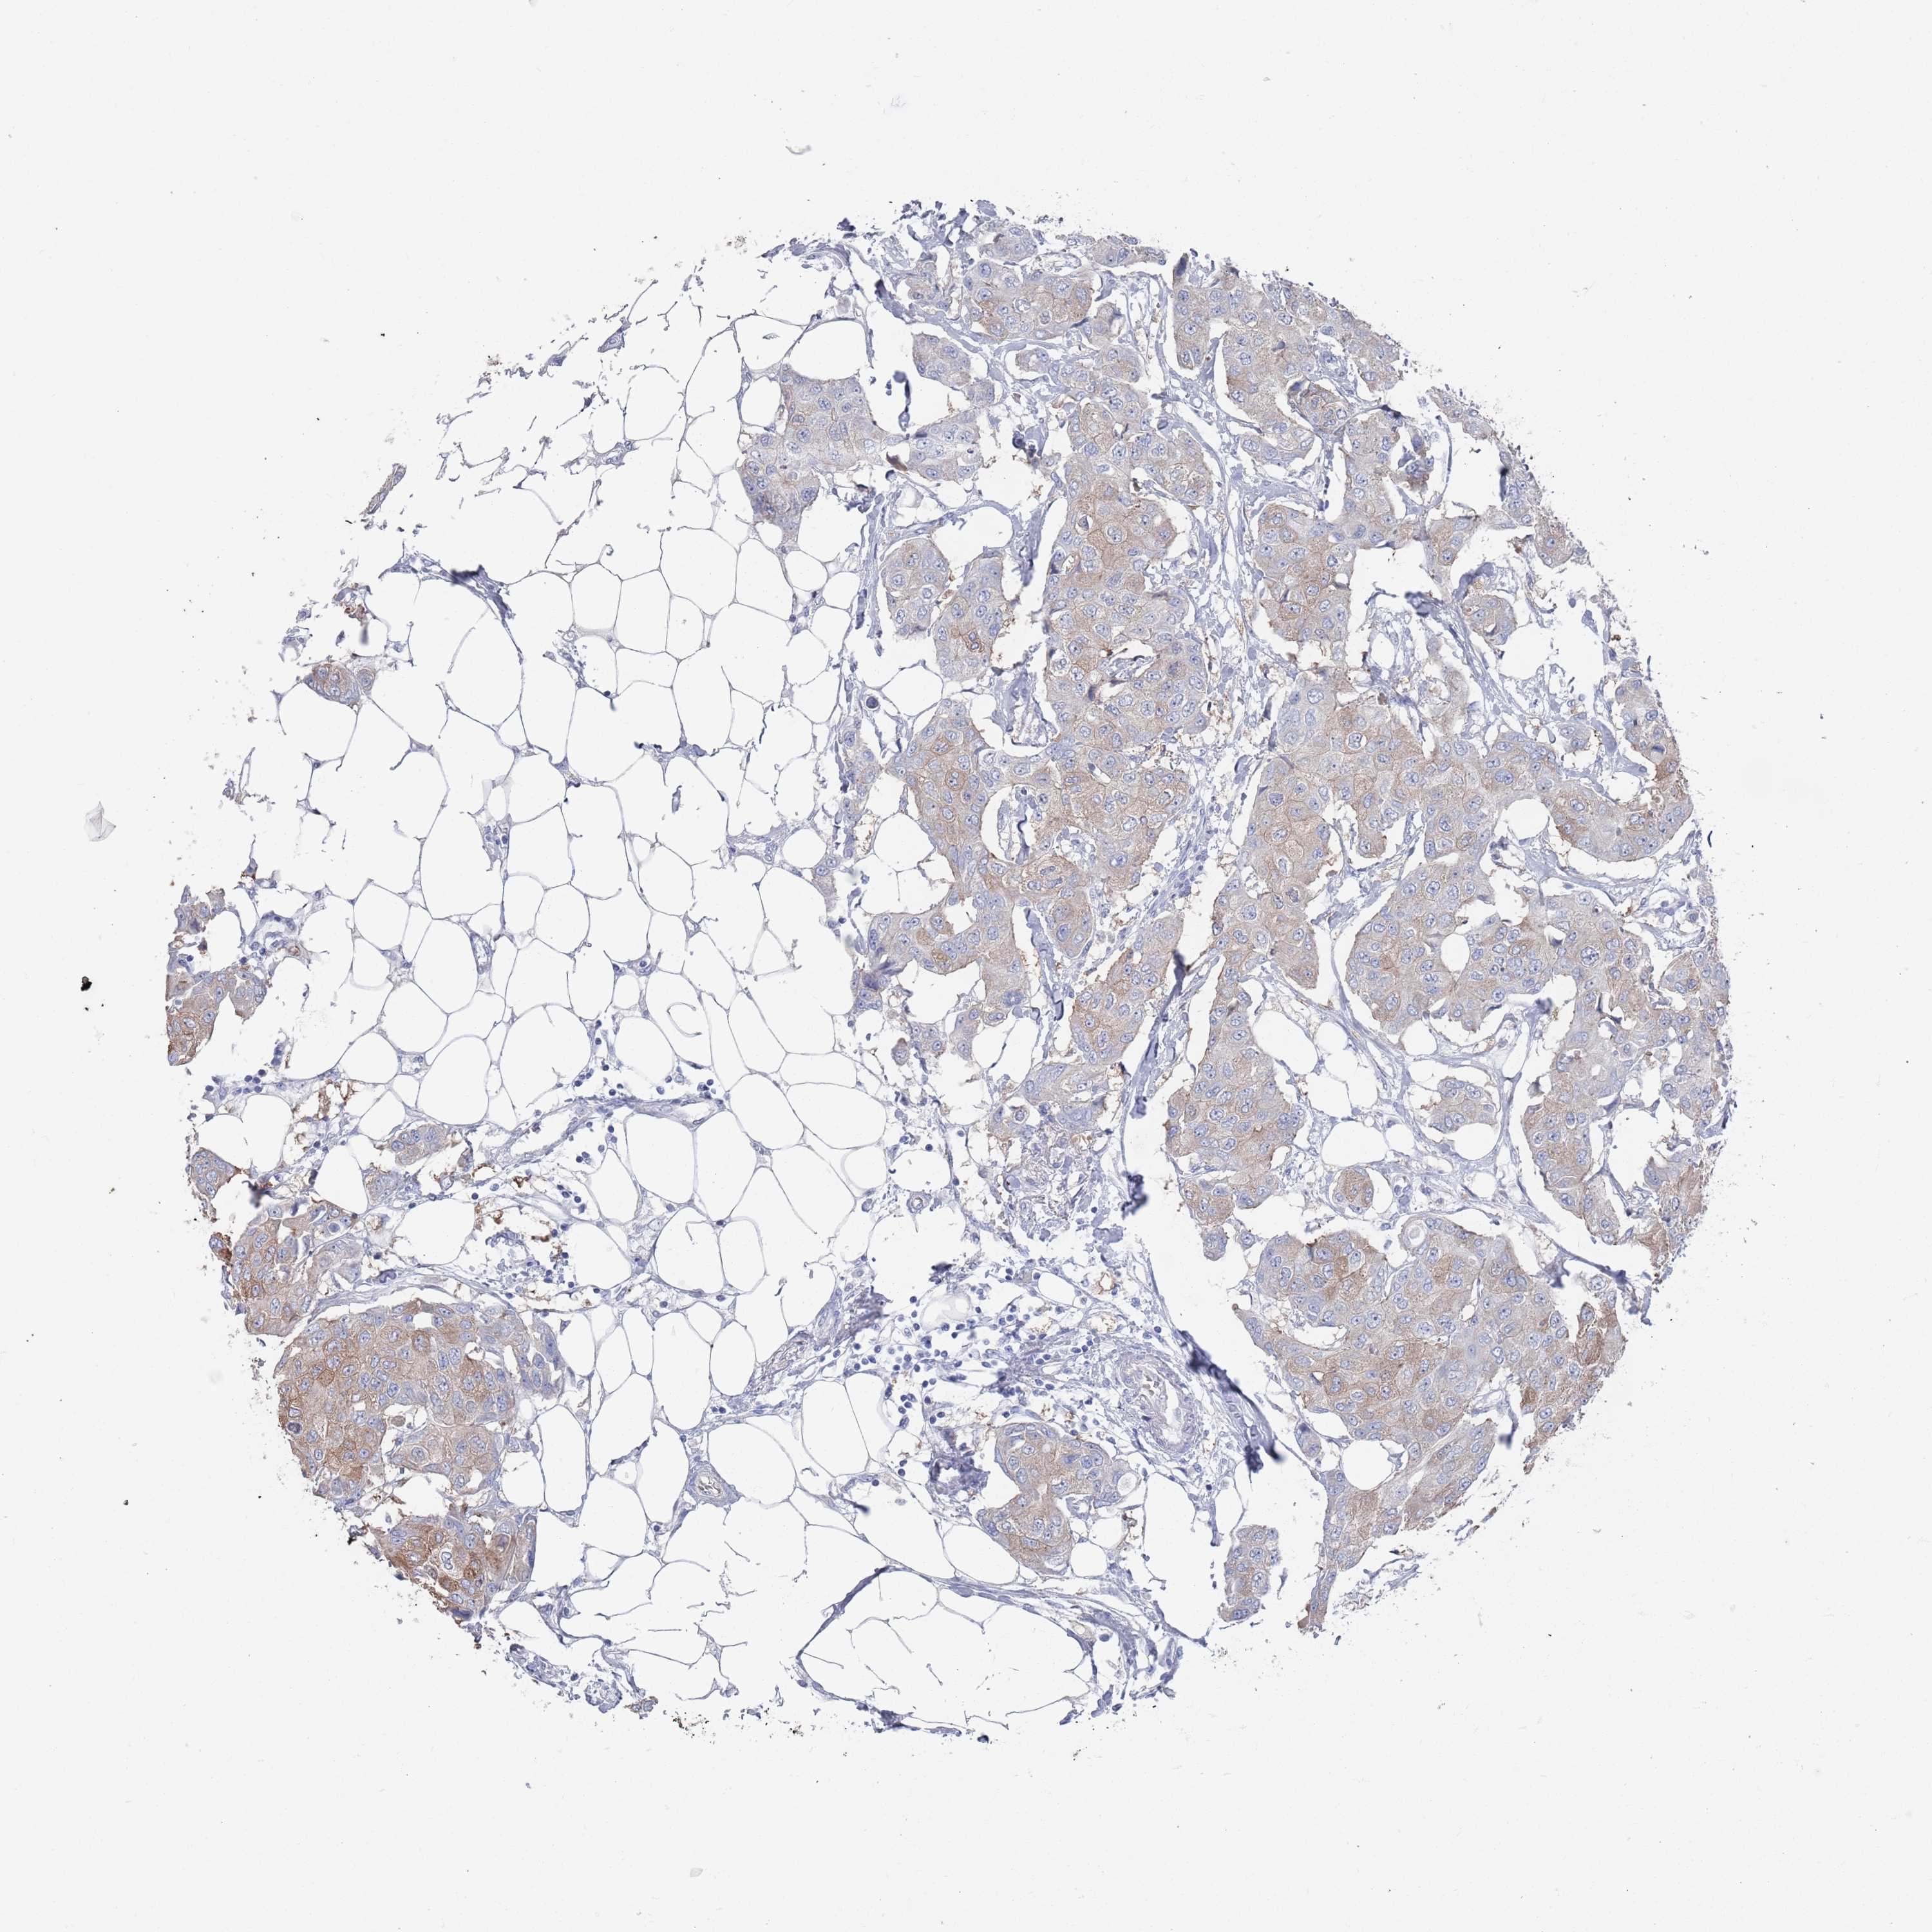

CANCER BREAST CANCER Show tissue menu

BRCA TCGA BRCA VALIDATION PROTEIN EXPRESSION